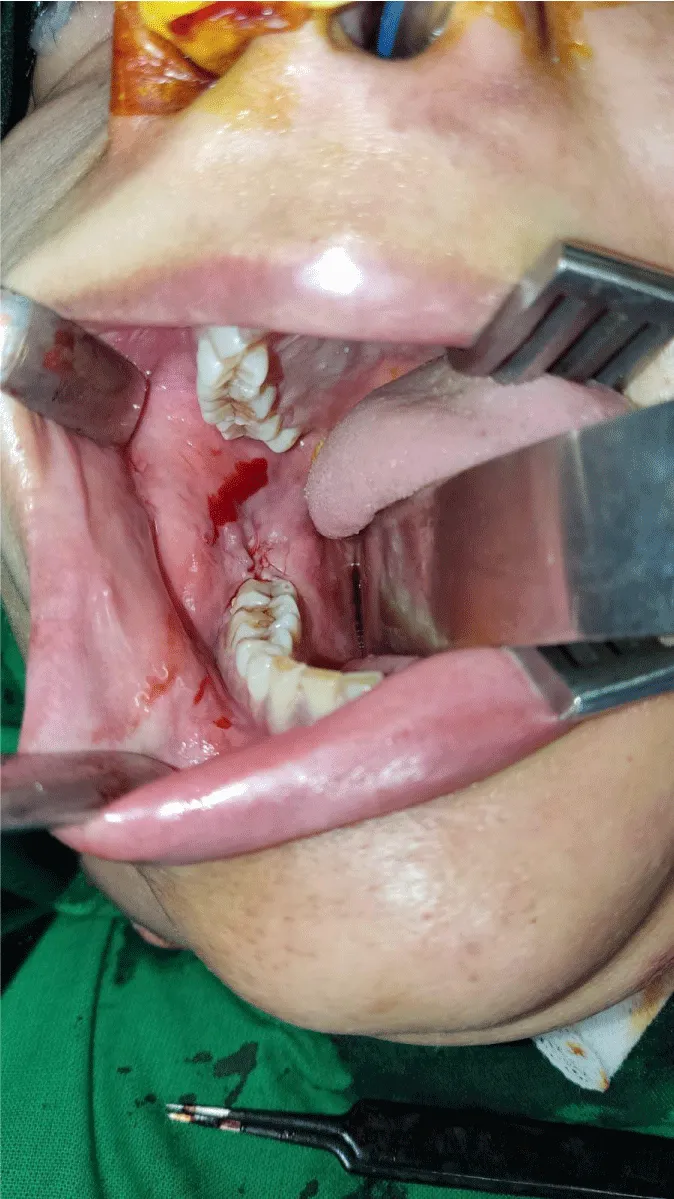

On examination, extra-orally a well-defined swelling on the right side of the face in the region of ramus and body of mandible resulting in facial asymmetry with normal smooth intact overlying skin (Figure 1). It measured about 6.0×4.3 cm hard in consistency and non-tender on palpation. There was no evidence of lymphadenopathy on either side of the neck. On intra-oral examination, there was a significant expansion of ramus and body of right mandible extending up to the right lower molar tooth causing obliteration of buccal vestibule with redness of overlying mucosa. There was no evidence of pussy discharge at the site of swelling (Figure 2).

After written and informed consent, baseline investigations, pre-operative workup, and general anesthesia fitness. She was booked for elective intra-oral surgery and shifted to Operation Theater. She underwent the complete surgical resection of the lesion with the extraction of involved teeth, enucleation, and curettage of the involved bone (Figure 8). The patient went through a smooth recovery with no drastic or minor complications on antibiotics and symptomatic treatment in the hospital postoperative course and on a follow-up visit. Post-operative radiological imaging showed no evidence of recurrent or residual lesions.